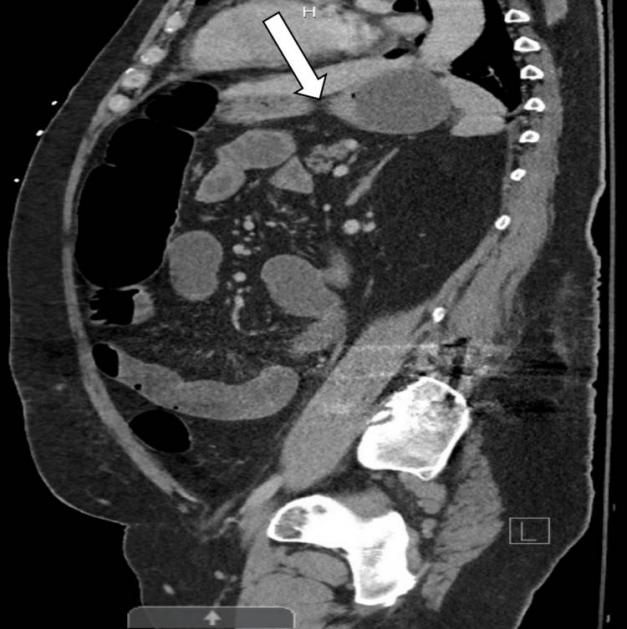

进行结肠减压最初改善了患者的症状,但第二天,患者出现了严重的腹痛和败血症,体温为39.6°C,窦性心动过速达130 bpm,白细胞增多。接受紧急剖腹探查术,证实了0.5cm的乙状结肠穿孔,并放置了网膜补片进行彻底修复。术后症状有所改善。术后第五天进行的重复CT腹部/骨盆静脉造影显示腹部预期术后变化,没有腹膜腔泄漏,结肠壁中度增厚,PI消退(图3)。患者完成了为期10天的哌拉西林/他唑巴坦静脉注射,总体状况有所改善。门诊随访显示恢复过程稳定。

图3腹部和骨盆的后续CT扫描显示,肠道大小正常,没有肠积气